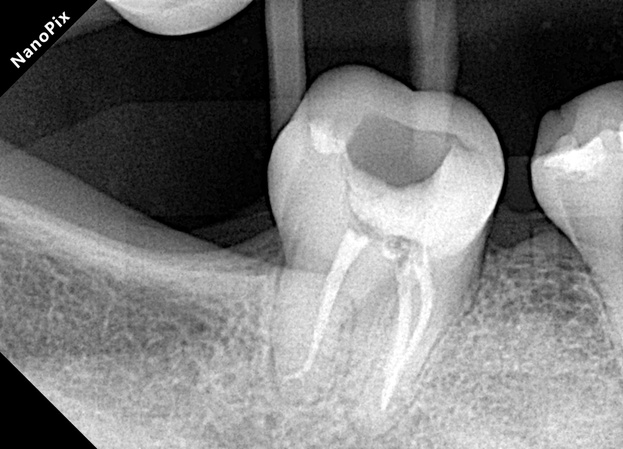

Este caso clínico intermedio del Dr. Néstor Salinas demuestra cómo una secuencia ordenada —negociación con limas K #10, patency apical, glide path con lima 016 Súper Flexi y conformación hasta 35/.04— permite resolver eficazmente una necrosis pulpar y periodontitis apical sintomática en un diente con restauración desadaptada y sobrecarga mecánica severa.

La combinación de técnica de fuerzas balanceadas y las propiedades de flexibilidad del sistema Súper Flexi resultó clave para lograr desinfección profunda y preservación anatómica, ofreciendo un protocolo reproducible para casos similares en endodoncia.